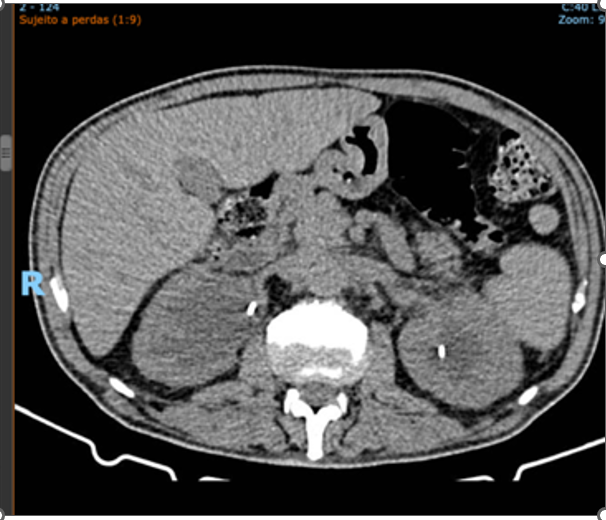

Figure 2. Total abdominal computed tomography: Examination performed at the onset of the condition, prior to treatment, showing bilateral hydronephrosis and a large retroperitoneal mass.